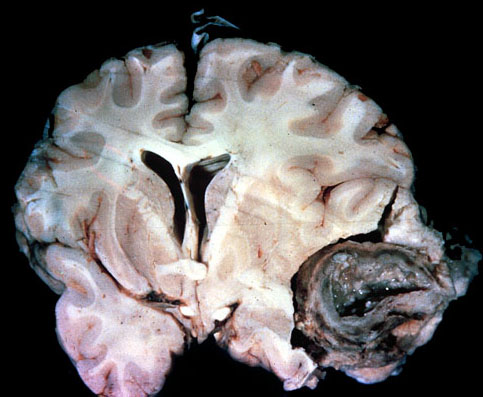

Temporal lobe

abscess

, complicating otitis media and mastoiditis.